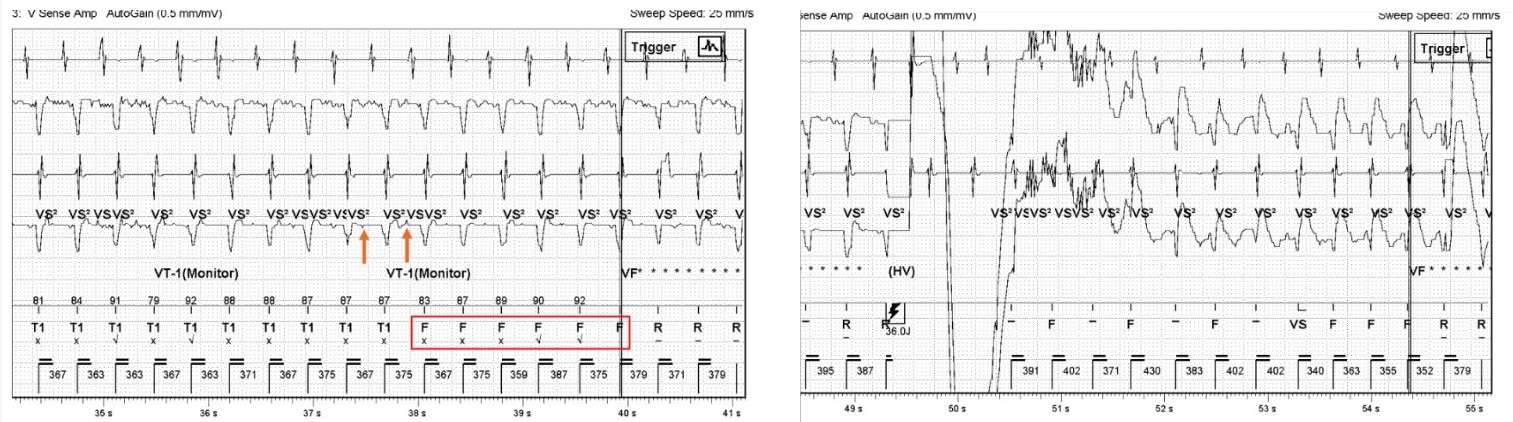

A 53-year-old male with heart failure with recovered ejection fraction (LVEF 45–50%) from non-ischemic cardiomyopathy, paroxysmal atrial fibrillation, and an Abbott CRT-D, experienced an unexpected ICD shock while performing light housework. He had no preceding symptoms. Device interrogation revealed a regular tachycardia at 160 bpm with low-amplitude ventricular signals on the far-field Coil-Can vector. These were misclassified by the VFTA algorithm as fine VF. Once triggered, VFTA collapsed all detection zones into a single therapy zone and suppressed supraventricular discriminators. Only six ventricular beats labeled “F,” each with a cycle length faster than 400 ms, were required to fulfill VF detection criteria, and a shock was delivered. SecureSense markers showed low-amplitude R-waves annotated as “VS2,” especially before “F” annotations (Figure 1). After identifying the mechanism, the sensing vector was reprogrammed from Coil-Can to Tip-Can, improving signal fidelity and preventing recurrence.